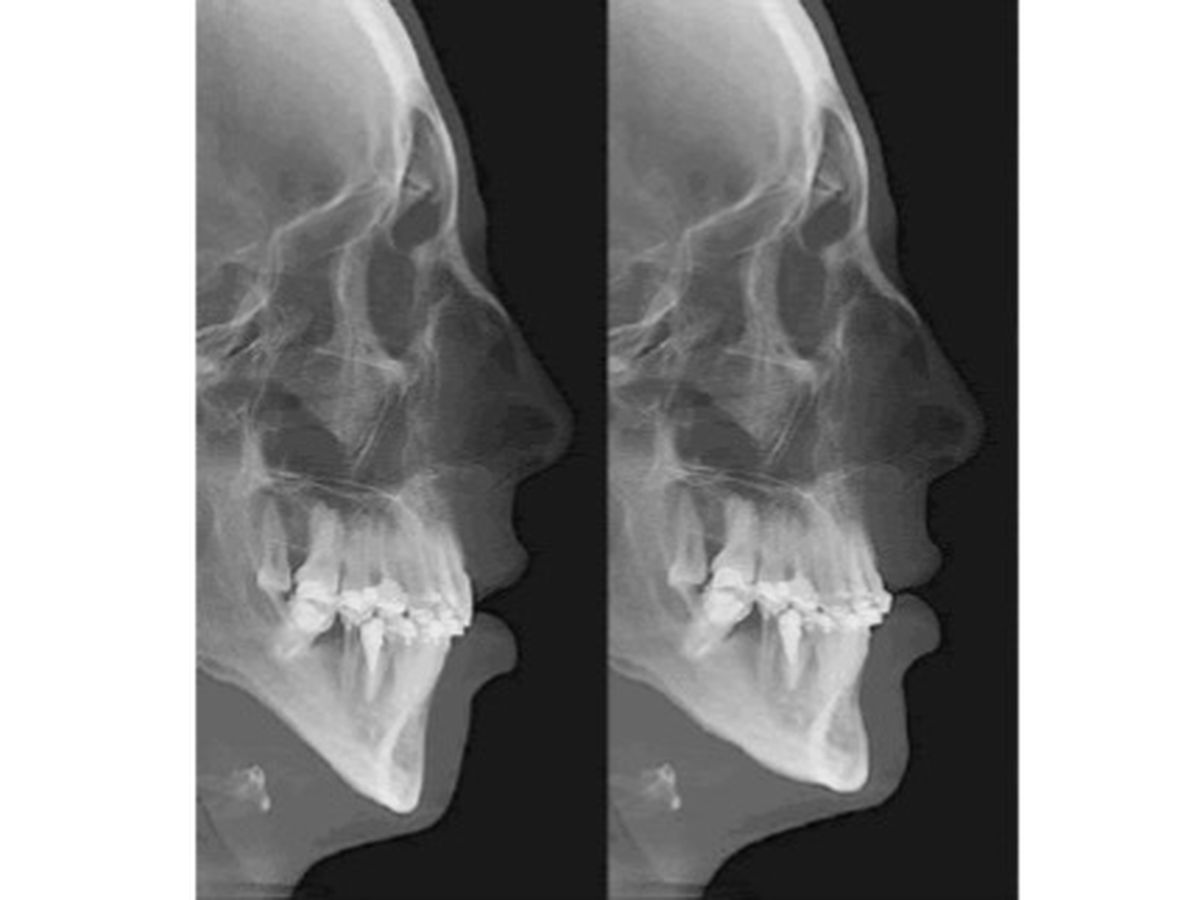

Last year, I was diagnosed with Obstructive Sleep Apnea. For those of you who don’t know what sleep apnea is, it’s where my airway is being blocked not allowing me to breathe properly, especially when I sleep. My jaw needs to be broken and repositioned as it is causing the blockage. I tried a CPAP for a long time before we figured out it was a fail. I then switched to a BIPAP and it has partially helped me to be able to sleep at night. This diagnosis has been disrupting my life.

The position of my jaw has caused the sleep apnea and has contributed to me grinding my teeth. I have almost no enamel left. It has caused my TMJ, and a lot of pain in my mouth. Most days it hurts to eat, smile and talk. It also contributes to my frequent headaches and migraines. Putting my jaw in the correct position would not only cure my sleep apnea, it would help straighten out all these other symptoms also.

Reconstructive jaw surgery will fix my sleep apnea and allow me to function back to normalcy.

Last year, I was diagnosed with Obstructive Sleep Apnea. For those of you who don’t know what sleep apnea is, it’s where my airway is being blocked not allowing me to breathe properly, especially when I sleep. My jaw needs to be broken and repositioned as it is causing the blockage. I tried a CPAP for a long time before we figured out it was a fail. I then switched to a BIPAP and it has partially helped me to be able to sleep at night. This diagnosis has been disrupting my life.

The position of my jaw has caused the sleep apnea and has contributed to me grinding my teeth. I have almost no enamel left. It has caused my TMJ, and a lot of pain in my mouth. Most days it hurts to eat, smile and talk. It also contributes to my frequent headaches and migraines. Putting my jaw in the correct position would not only cure my sleep apnea, it would help straighten out all these other symptoms also.

Reconstructive jaw surgery will fix my sleep apnea and allow me to function back to normalcy.